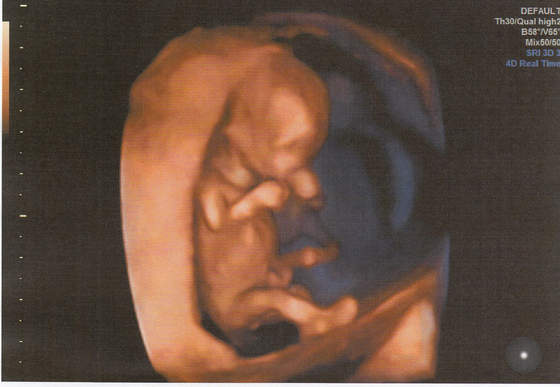

Hej ja po wizycie, bąbel młodszy o 2 dni niz z OM wiec mam sie za tydz pokazac na przeziernosc. Reszta ok, raczki, nozki, zoladek itd itd. Maluch ma 4,84 cm. Ja w pt ide na dokladne usg to moze cosik sie uda podgladnac a na razie taka tylko fotka na szybko. Tak sie wiercil maluch ze nie mozna bylo zrobic ladnego zdjecia